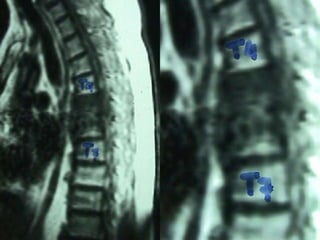

MRI

Unknown origin

3